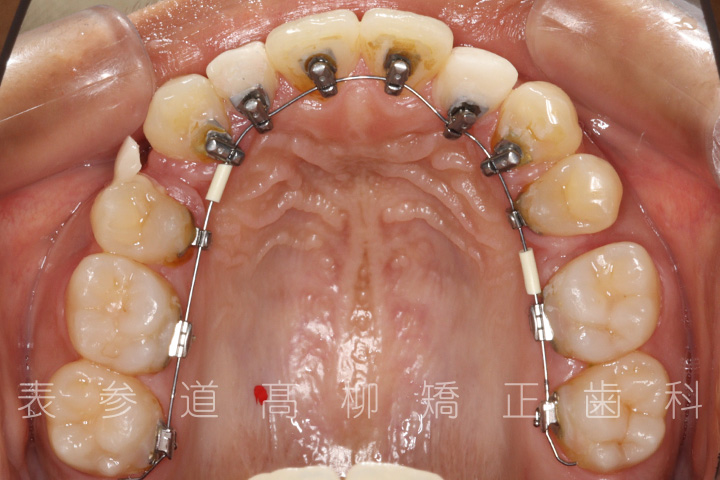

治療に用いた主な装置

・リンガルブラケット装置

・歯科矯正用アンカースクリュー

・アライナー